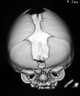

Apert syndrome is a form of acrocephalosyndactyly, a congenital disorder characterized by malformations of the skull, face, hands and feet. It is classified as a branchial arch syndrome, affecting the first branchial (or pharyngeal) arch, the precursor of the maxilla and mandible. [Source: Wikipedia ]

Craniosynostosis